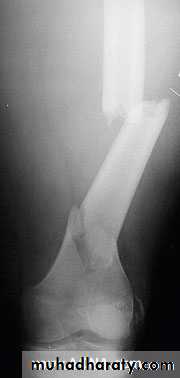

8Types

Transverse : tension or direct force

Butterfly fragment : bending

Short oblique : compression

Long oblique : indirect force

Spiral : twisting